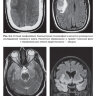

Примеры страниц из книги"Лучевая диагностика при заболеваниях системы крови" - Е. В. Крюкова, Д. В. Давыдова